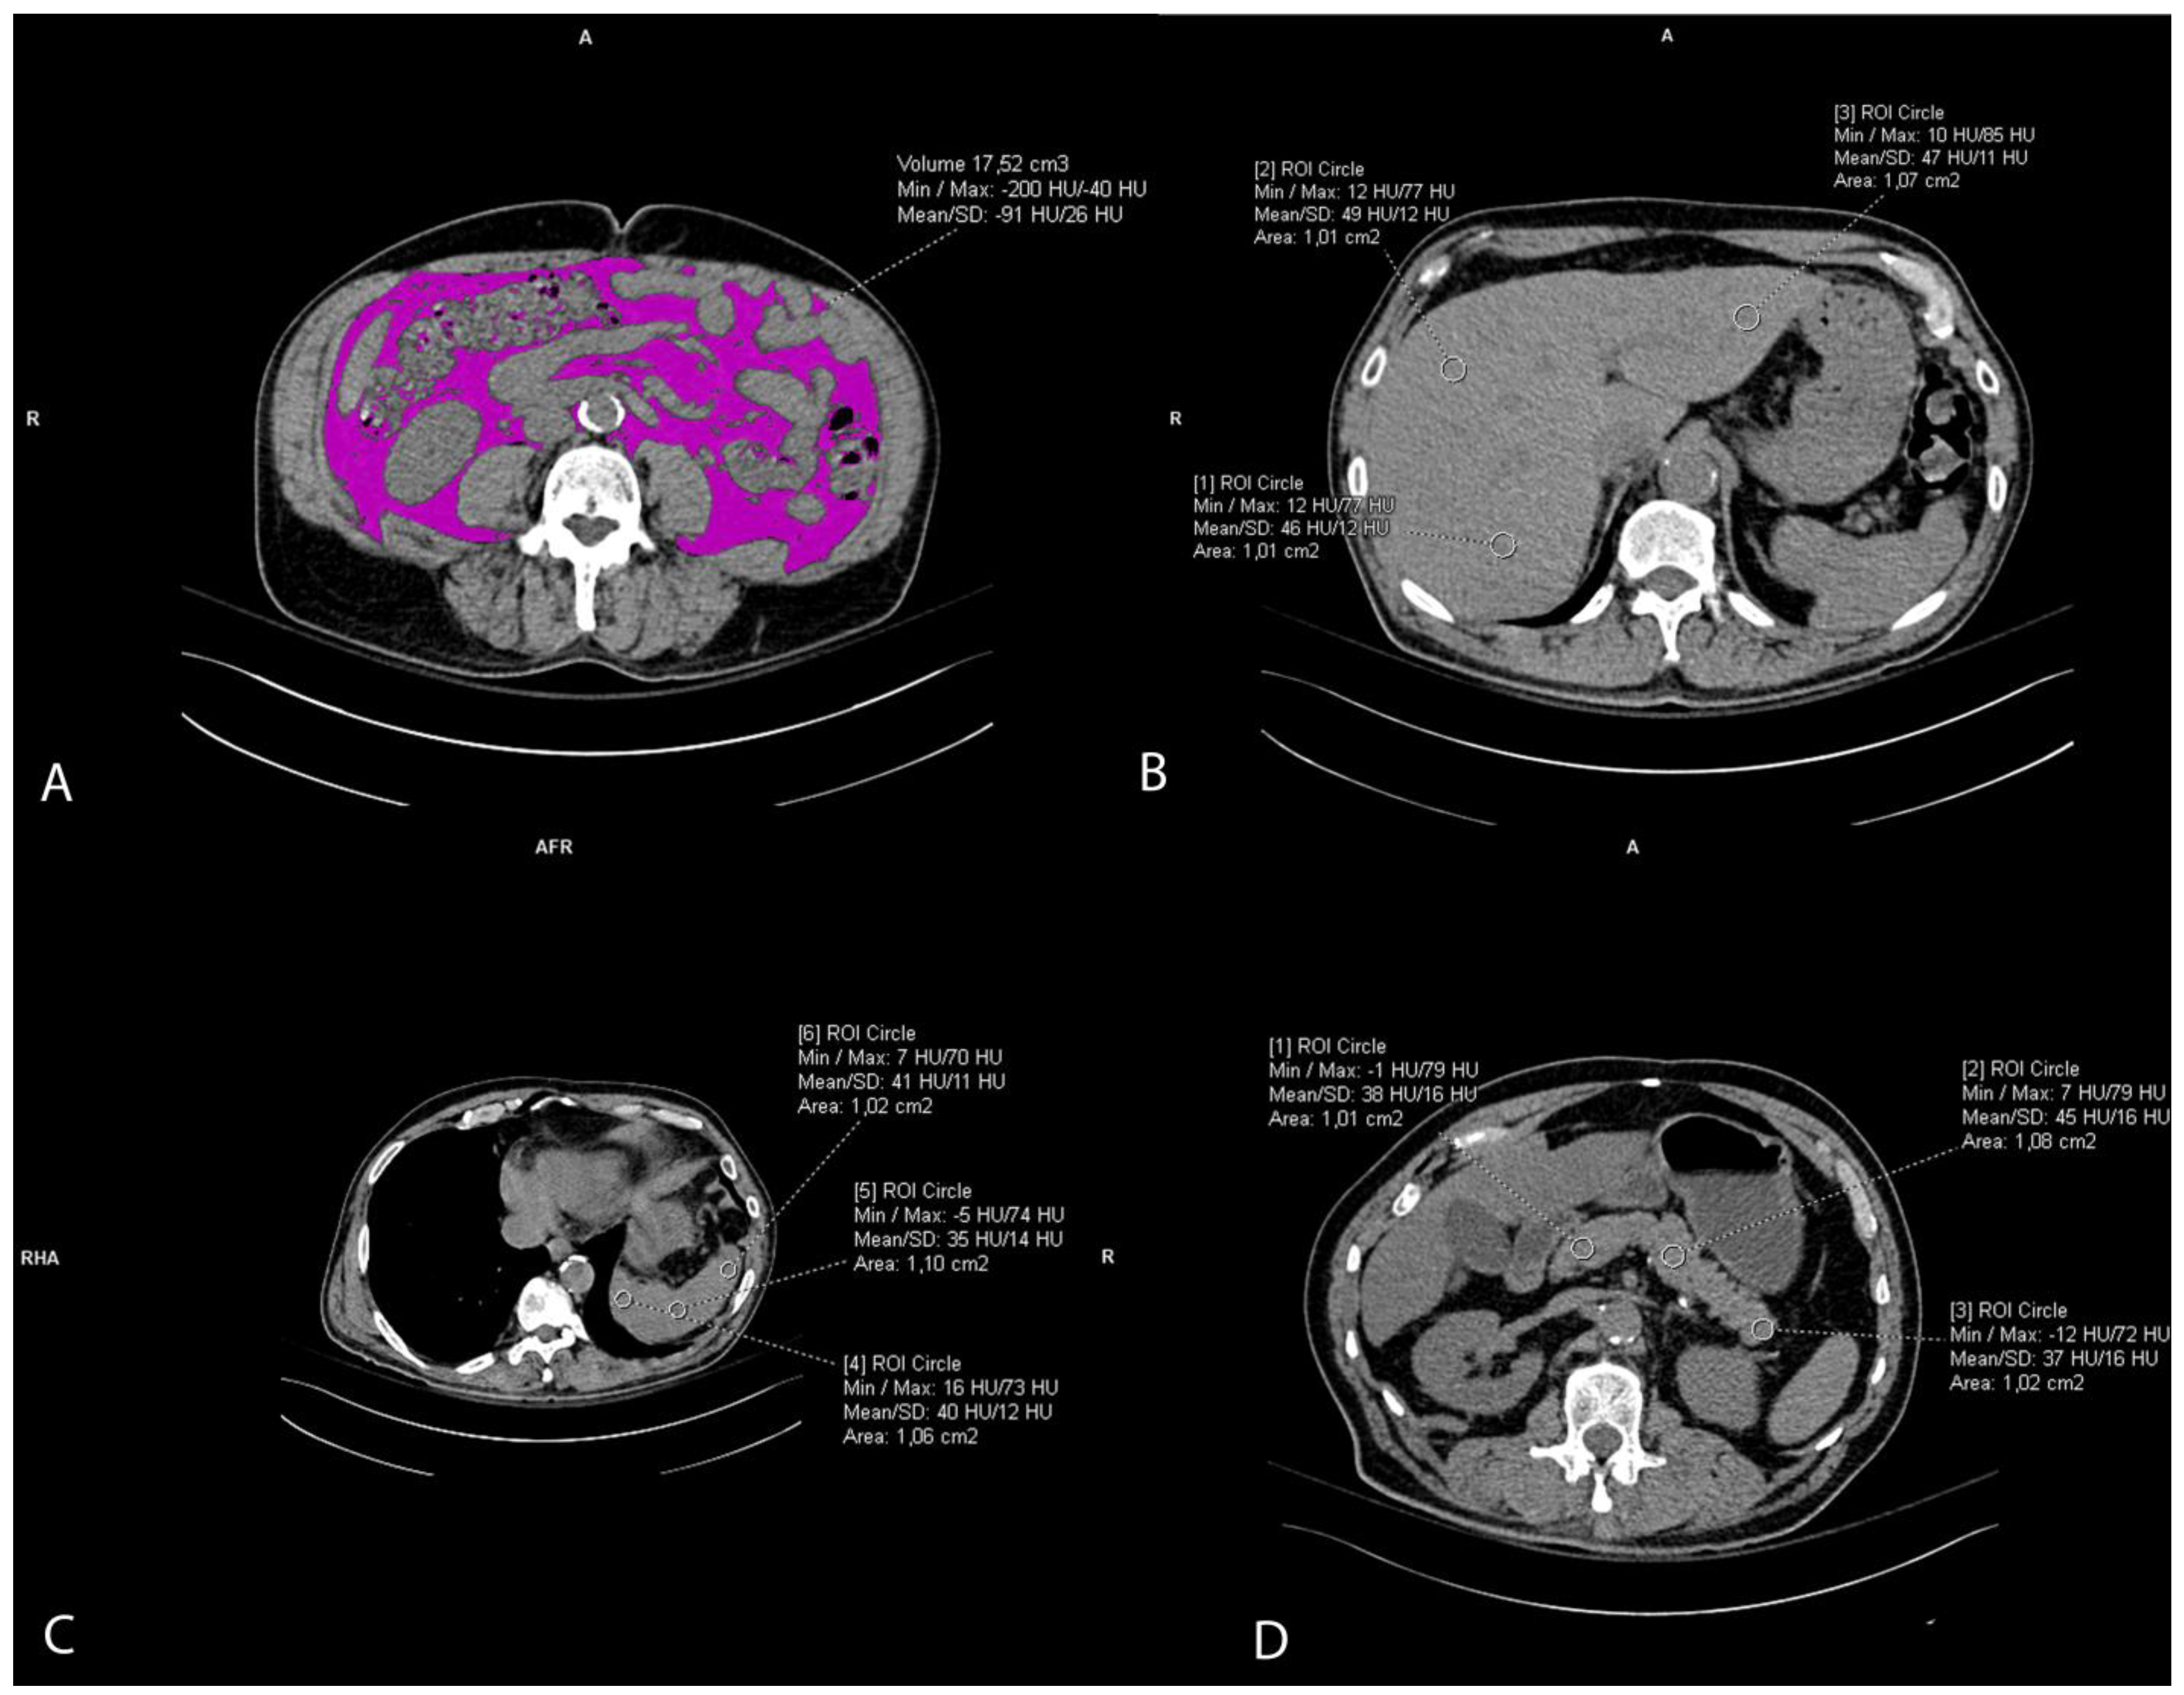

2.3. Visceral Fat Volume Measurement

The visceral fat volume, expressed in cm3, was measured on the native/pre-contrast CT scans of the abdomen and pelvis semiautomatically. First, at the umbilical level, a line at the inner contour of the abdominal muscles was carefully manually drawn. The Hounsfield unit of fat tissue attenuation from −200 and −40 HU was automatically segmented within this area surrounded by the manually drawn line. Finally, the visceral fat volume was automatically calculated by the Siemens syngo.via VB60A_HF08 software (Figure 2A). The intraclass correlation coefficient (ICC) was 0.982 (95% CI 0.96–0.99).

Figure 2. Representative axial CT images showing visceral fat volume estimation (A), liver attenuation measurement (B), spleen attenuation measurement (C), and pancreas attenuation measurement (D).

2.4. Ectopic Fat Accumulation Measurements

Liver attenuation was measured by drawing three round regions of interest (ROI) of the approximately same size, 1 cm2, at the portal vein level representing HU. The ROI was placed within the left lobe, right anterior lobe, and right posterior lobe of the liver. All ROIs were carefully distributed in the liver parenchyma, excluding the biliary, vascular, and other structures. (Figure 2B). The used liver attenuation was an average of the three HU at the mentioned measurement sites. Spleen attenuation was very similarly measured by averaging three manually placed round ROIs (approximately 1 cm2), representing HU, at three different areas of spleen on the same slice (Figure 2C). After the liver and spleen attenuation measurements, the liver-to-spleen attenuation ratio was calculated by dividing the average liver with average spleen attenuation. The index was used as a measure of ectopic fat accumulation in the liver parenchyma (liver steatosis). Pancreas attenuation measurement was similarly performed using ROI at the pancreatic parenchyma at the uncinate process, and the head, neck, body, and tail of the pancreas (Figure 2D). An average of the HU in the pancreas was calculated, and then the pancreas-to-spleen attenuation ratio was calculated in the same manner, by dividing the mean attenuation values of the pancreas and spleen. The pancreas-to-spleen attenuation was used as a measure of ectopic pancreatic fat accumulation (pancreatic steatosis). The ICC for the liver-to-spleen ratio was 0.939 (95% CI 0.80–0.97), and for the pancreas-to-spleen ratio it was 0.852 (95% CI 0.71–0.93).